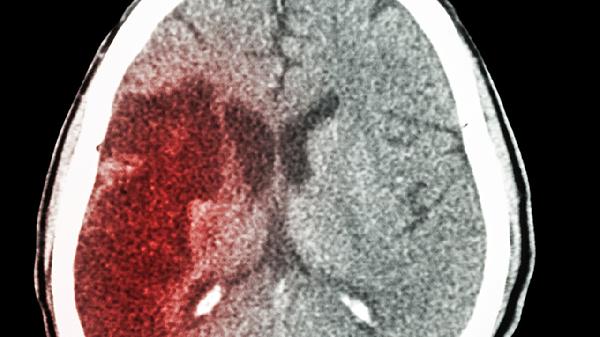

创伤性脑损伤、颅内肿瘤或中枢神经系统感染可能破坏脑脊液吸收平衡。这类患者常伴有头痛、呕吐等颅高压症状,需通过头颅CT明确病因后针对性治疗,如肿瘤切除或抗感染治疗。

脑室腹腔分流术是主流治疗方式,通过植入分流管将多余脑脊液引流至腹腔。手术成功率约85%,但可能存在分流管堵塞、感染等并发症,术后需定期复查CT并监测颅内压变化。